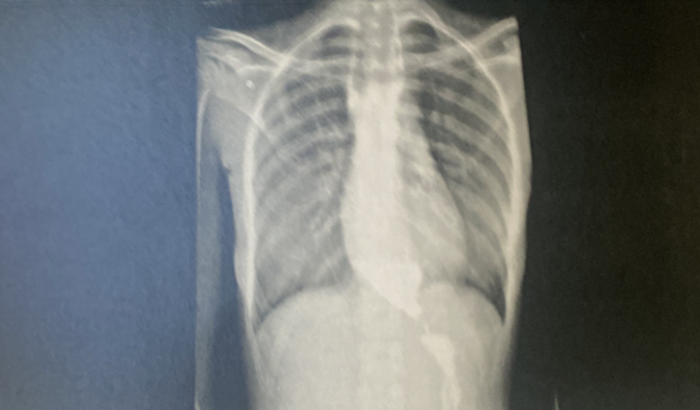

Olá! Como vai?! Como muitos sabem estou com um sério problema no esôfago e vou precisar me submeter a um procedimento no mesmo. Decidi criar essa vaquinha para obter ajuda com a anestesia e custos do pós operatório. Muitas pessoas me disseram “se precisar de alguma coisa é só falar.” então estou precisando. Esse problema no esôfago impede que eu me alimente como qualquer pessoa normal, impede que eu beba a quantidade de água necessária e mediante a isso vem juntos outros problemas como a desnutrição e a desidratação. Conto com a sua ajuda pra enfrentar esse problema e deixarei todos a par da situação no meu Instagram e no WhatsApp. Não importa o valor, doe o quanto puder e o quanto sua realidade permitir! Obrigada a todos! Deus abençoe vocês! 🧡